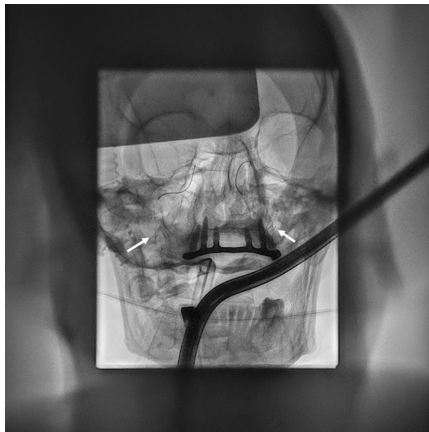

脑保护技术创新

在缺乏专用脑保护装置情况下,团队将颈动脉支架植入术中的Emboshield NAV6系统(图2)改造为"双滤器屏障"。这种离轴设计既能拦截脱落的血栓碎片,又避免了传统保护装置需要预判栓塞路径的局限性。术后CT证实该策略成功预防了脑栓塞(图3a),尽管意外发现髂静脉存在原发血栓(图3b)。